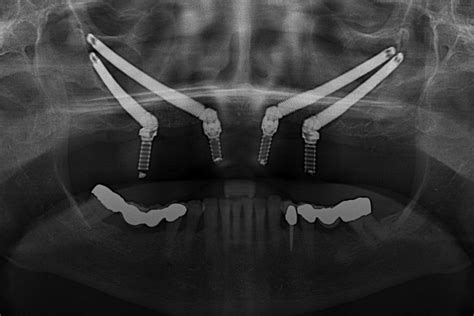

Los implantes cigomáticos, originariamente diseñados por Branemark en 1989, son implantes de cabeza en 45 grados, de 4'5 milímetros de diámetro en su parte más ancha, y que pueden medir entre 30 y 50 milímetros de longitud. Se insertan desde la parte palatina del proceso alveolar, siguiendo la cresta cigomática-alveolar hasta anclarse en el cuerpo del malar, y en el caso de pacientes maxilectomizados, entrando directamente en el cuerpo del malar. Estos implantes ofrecen una alternativa más al cirujano en el momento de planificar un tratamiento protésico-rehabilitador implantosoportado. Sobretodo, en aquellos pacientes con un maxilar superior atrófico en el que no se pueden realizar injertos óseos o estos han fracasado.

Se realizará un examen radiológico lo más completo posible con la finalidad de excluir patologías en ambos maxilares, detectar la forma y extensión de los senos maxilares, descartar posibles patologías en los mismos que podrían contraindicar o retrasar la inter- la parte frontal del maxilar superior, en el hueso cigomático, y a nivel del proceso alveolar a la altura de la región premolar. Es importante también determinar la topografía de la pared anterior de la fosa temporal, descartando la presencia de concavidades .

El examen radiológico incluirá una ortopantomografia, una proyección de Waters y una tomografía computadorizada (TC) del maxilar superior y del hueso malar, a partir de la cual podemos hacer una reconstrucción tridimensional o un modelo estereolitográfico. En este modelo podemos simular la cirugía de este paciente de forma virtual, de manera que llegaremos al quirófano con un conocimiento exhaustivo de la anatomía y dimensiones óseas de este paciente en particular, lo cual favorecerá nuestra orientación tridimensional.